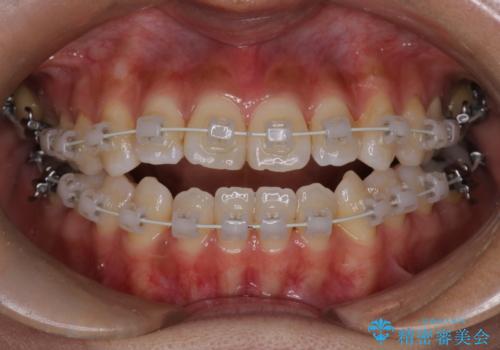

- 開咬を主訴に来院されました。前歯部に開咬、右側大臼歯部にクロスバイトが認められます。ワイヤー矯正の審美装置で治療し、ゴム掛けを行いながら噛み合わせを改善しました。

主訴である開咬と右側大臼歯部クロスバイトを改善でき、しっかりと噛むことができるようになりました。